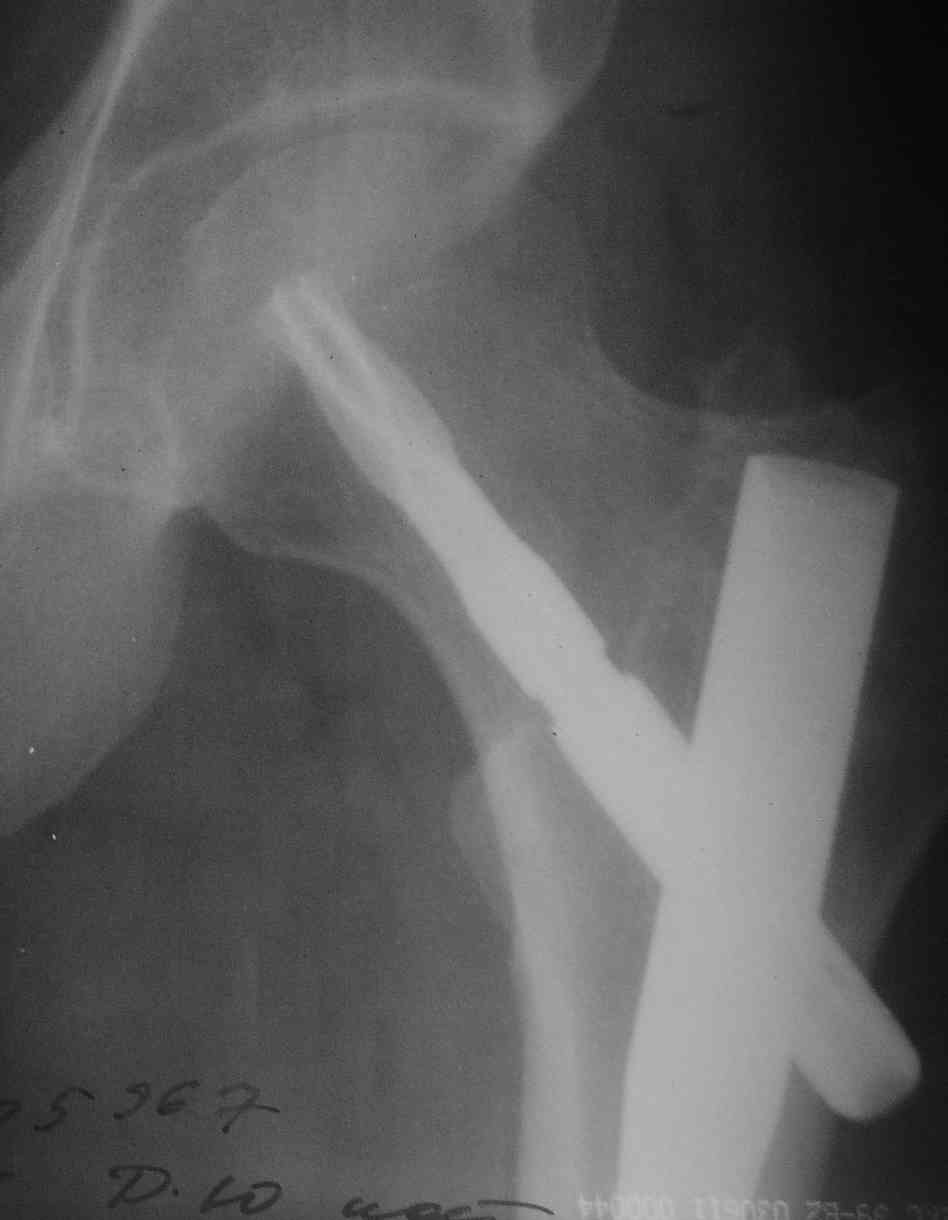

Re: Удаление PFN-A

послал Alexander Chelnokov 25 Июль 2007, 01:42

> Был ли это клинок вскрыт из упаковки только на операции

Да.

> Вспонинаются ли какие-нибудь технические трудности/проблемы при первичной

> операции?

Не удалось его заблокировать. Так он и не сомкнулся.

> В том что он хорошо держится в губчатой кости - одна из "проблем".

Ну не до такой же степени...

>> Есть ли возможность удалить остальную часть клинка и гвоздь?

> А какие были показания для удаления?

Желание пациента.

> Можно увидеть еще снимки: до , после....? Что за субъект?

Молодой мужик, была множественная травма. Снимок перед удалением вот.